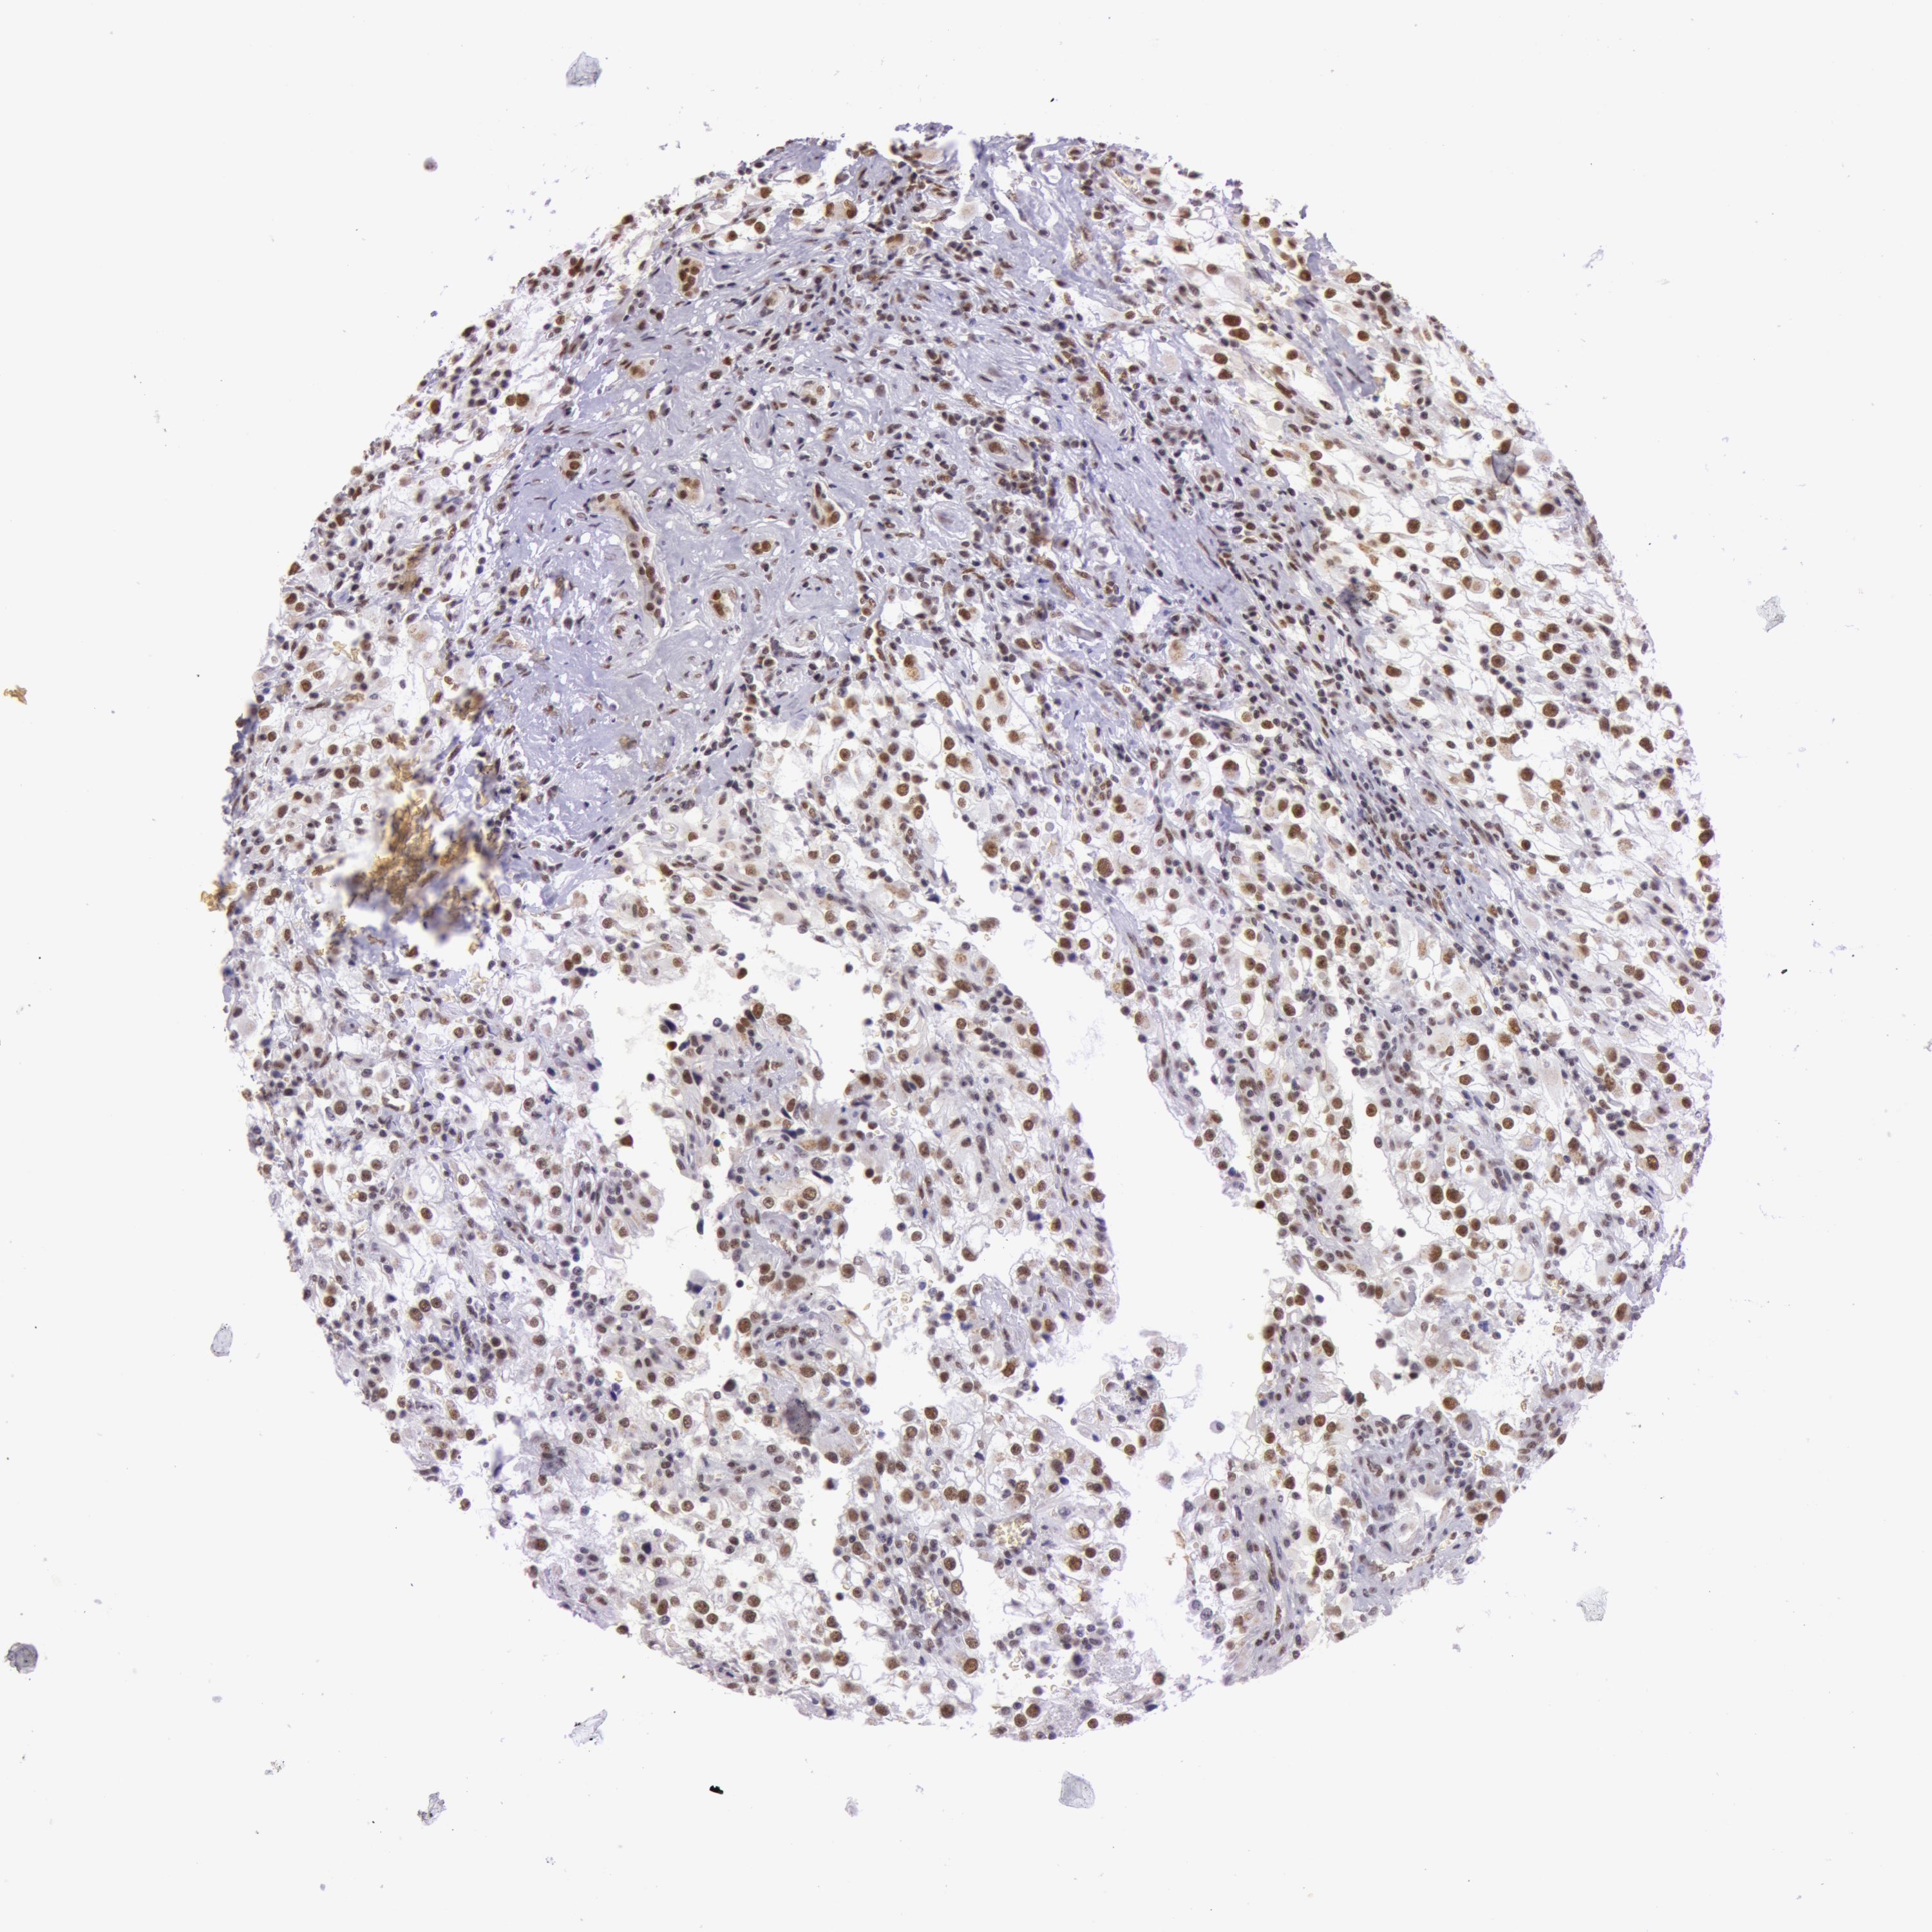

KIDNEY RENAL CLEAR CELL CARCINOMA (VALIDATION) - Interactive survival scatter ploti

The Survival Scatter plot shows the clinical status (i.e. dead or alive) for all individuals in the patient cohort, based on the same data that underlies the corresponding Kaplan-Meier plots. Patients that are alive at last time for follow-up are shown in blue and patients who have died during the study are shown in red.

The x-axis shows the expression levels (FPKM) of the investigated gene in the tumor tissue at the time of diagnosis. The y-axis shows the follow-up time after diagnosis (years). Both axes are complimented with kernel density curves demonstrating the data density over the axes. The top density plot shows the expression levels (FPKM) distribution among dead (red) and alive patients (blue). The right density plot shows the data density of the survived years of dead patients with high and low expression levels respectively, stratified using the cutoff indicated by the vertical dashed line through the Survival Scatter plot. This cutoff is automatically defined based on the FPKM cutoff that minimizes the p-score. The cutoff can be changed by dragging the vertical line or by entering a cutoff value in the square labeled "Current cut-off".

Under the Survival Scatter plot the p-score landscape (black curve; left axis) is shown together with dead median separation (red curve; right axis). Dead median separation is the difference in median mRNA expression between patients who have died with high and low expression, respectively. It is calculated as follows: median FPKM expression of dead patients with high expression - median FPKM expression of dead patients with low expression. This is intended to aid the user in visually exploring custom cutoffs and the associated p-scores and dead median separation.

Individual patient data is displayed and can be filtered by clicking on one or more of the category buttons on the top of the page. Categories describing expression level and patient information include: high, low, alive, dead, female, male and tumor stages. The scale of the x-axis can be toggled between linear and log-scale by clicking on the "x log" button. Mouse-over function shows TCGA ID, patient information and mRNA expression (FPKM) for each patient.

& Survival analysisi

Kaplan-Meier plots summarize results from analysis of correlation between mRNA expression level and patient survival. Patients were divided based on level of expression into one of the two groups "low" (under cut off) or "high" (over cut off). X-axis shows time for survival (years) and y-axis shows the probability of survival, where 1.0 corresponds to 100 percent.

NBN is not prognostic in Kidney Renal Clear Cell Carcinoma (validation)

Best expression cut offi

Based on the FPKM value of each gene, patients were classified into two groups and association between prognosis (survival) and gene expression (FPKM) was examined. The best expression cut-off refers the FPKM value that yields maximal difference with regard to survival between the two groups at the lowest log-rank P-value. Best expression cut-off was selected based on survival analysis .

When clicking on this number, the vertical dashed line indicating cut-off, the interactive survival plot, and the Kaplan-Meier curve will be adjusted to show results based on the best expression cut-off.

: 28.6

P scorei

Log-rank P value for Kaplan-Meier plot showing results from analysis of correlation between mRNA expression level and patient survival.

N/A

TCGA RNA samplesi

RNA-seq data is reported as average FPKM (number Fragments Per Kilobase of exon per Million reads), generated by the The Cancer Genome Atlas (TCGA) .

Normal distribution across the dataset is visualized with box plots, shown as median and 25th and 75th percentiles. Points are displayed as outliers if they are above or below 1.5 times the interquartile range. FPKM values of the individual samples are presented next to the box plot.

Average pTPM 43.2

Number of samples 100